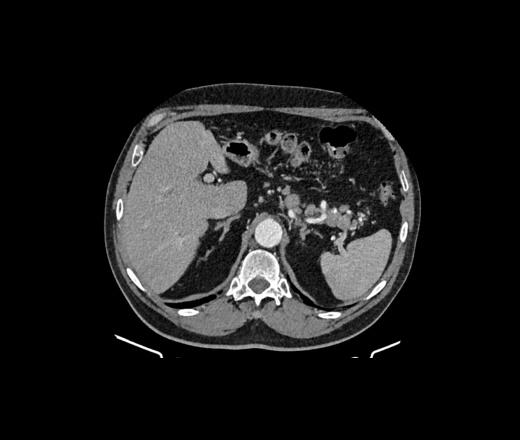

Здравствуйте, подскажите пациент 60 лет, особо жалоб нет, на узи было изменения в печени, в хвосте поджелудочной железы отмечаются немного гиподенсивные изменения может ли это быть раком? на МРТ лучше покажет?

В печени гиперваскулярное образование в 5 сугменте, требует наблюдения. Поджелудочная - ничего плохого не вижу. А вот лимфоаденопатия выражена. Если мтс, то откуда - не знаю